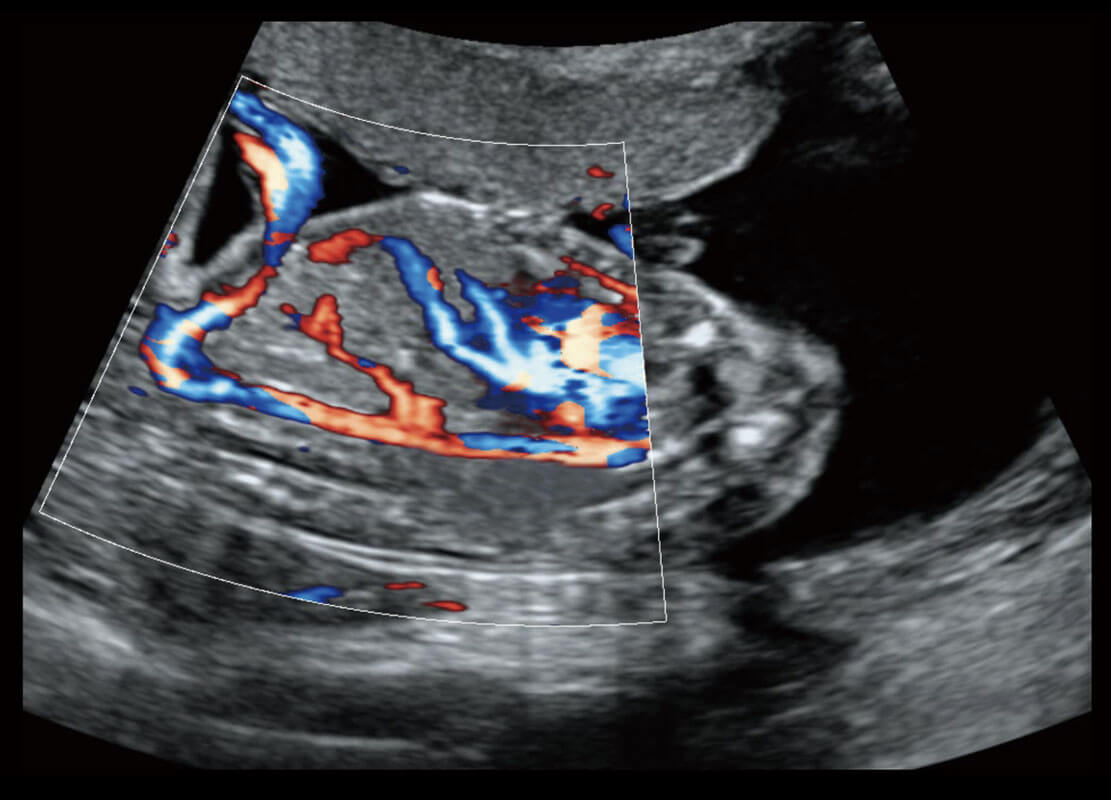

新生儿脊髓圆锥

新生儿心脏

P60搭载宽频带线阵探头、宽景成像、弹性成像技术,为您提供乳腺应用方案。P60支持高频相控阵探头、线阵探头、腹部高频探头、腹部微凸探头等,丰富的探头群搭载敏感的彩色血流成像,适用于新生儿多种脏器检测要求,满足新生儿筛查需求。